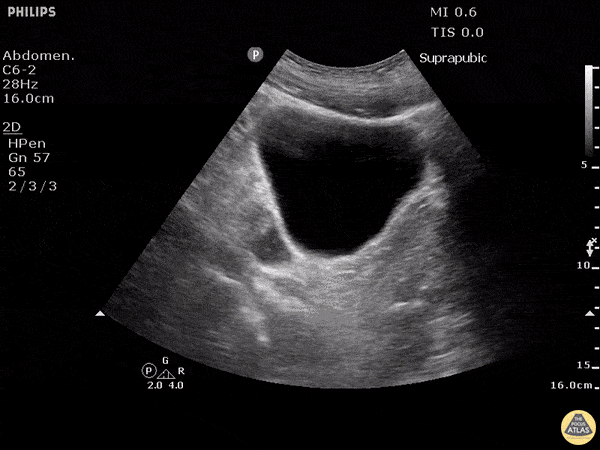

Blunt trauma patient with POSITIVE FAST scan. Free fluid can be seen posterior and lateral to the bladder in this sagittal view. Dr. Justin Bowra